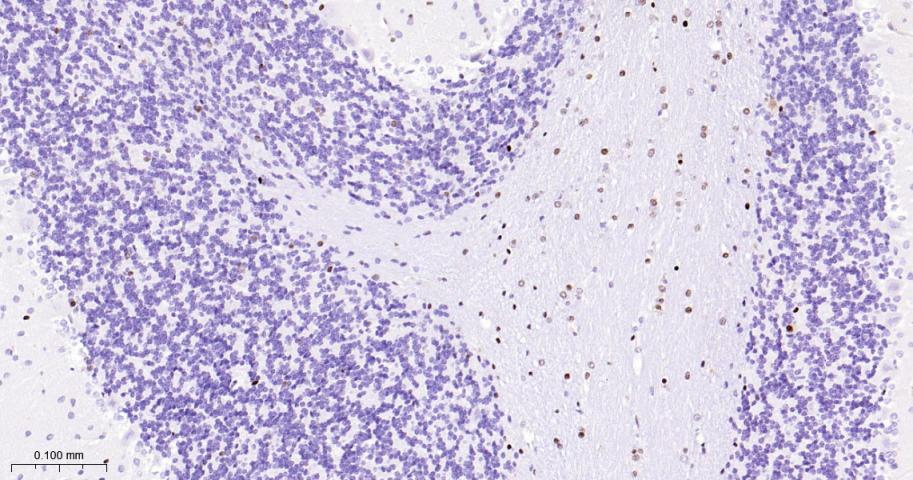

| IHC-P | Human, Mouse, Rat | 1:200-800 | |

| IHC-F | Human, Mouse, Rat | 1:200-800 | |